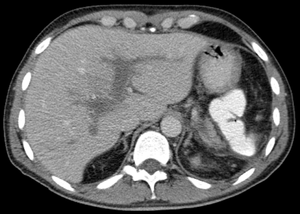

| Portal vein thrombosis seen with computed tomography. | |

The diagnosis of portal vein thrombosis is usually made by ultrasound, computed tomography with contrast or magnetic resonance imaging. D-dimer levels in the blood may be elevated as a result of fibrin degradation.